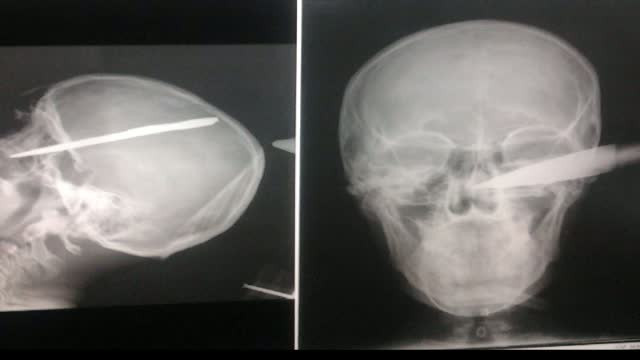

Povestea unui miracol. Cum a supravietuit un tanar de 20 de ani din Bucuresti cu sabie in craniu

In mod miraculos, un tanar de 20 de ani din Bucuresti a scapat cu viata, dupa ce o sabie i-a strapuns craniul.